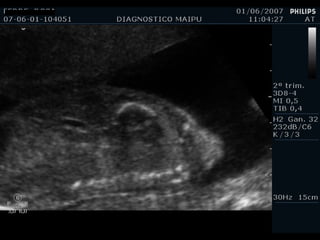

Evaluación del corazón fetal en la ecografía obstétrica Modo B ¿CUANDO? Segundo y tercer trimestres ¿Como? De mayor a menor

1) LONGITUDINAL / CEFALICA / DORSO IZQ

2) LONGITUDINAL / PODALICA / DORSO DER